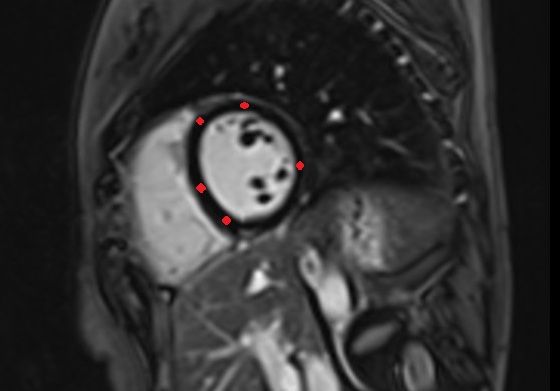

- Heart

- Left ventricle

- Left atrium

- Interventricular Septum